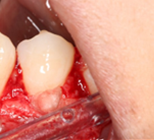

Surgical management of external cervical resorption lesion

Pre-op X-ray

Procedure Photos